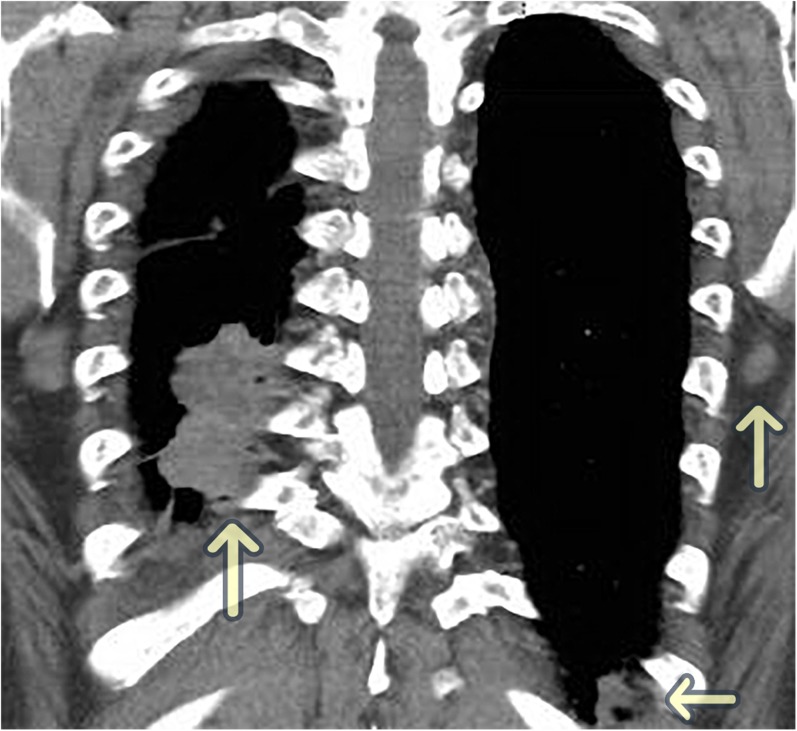

Figure 1.

CT chest, abdomen, pelvis: multinodular, conglomerate pleural based mass of the right lower lobe and right lung base as well as two pleural based left nodules.